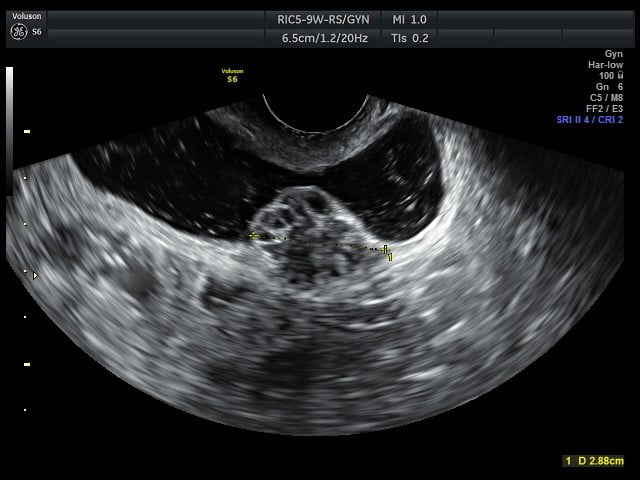

sintomas de endometriose

Endometriose na bexiga, com 2,88 cm de extensão, identificada no exame de ultrassonografia transvaginal.